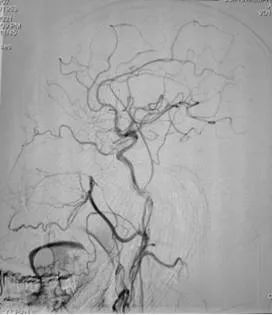

脑病介入科曹骅主任、赵宏廷主治医师先进行左侧颈外动脉血管造影,以明确复杂瘘口,术前造影:颈外动脉中包括枕动脉、耳后动脉、颞浅动脉的多个分支通过硬脑膜向颅内静脉形成异常引流,栓塞术难道很大。

手术过程:术中采取弹簧圈辅助填塞,Onyx液态胶多支供血动脉分次栓塞治疗措施,由于供血动脉纵横交错,手术难道可想而知,经过4小时的艰难努力,于18:30手术结束,术程顺利,成功帮助患者填塞了动静脉瘘,为患者解决了病痛。